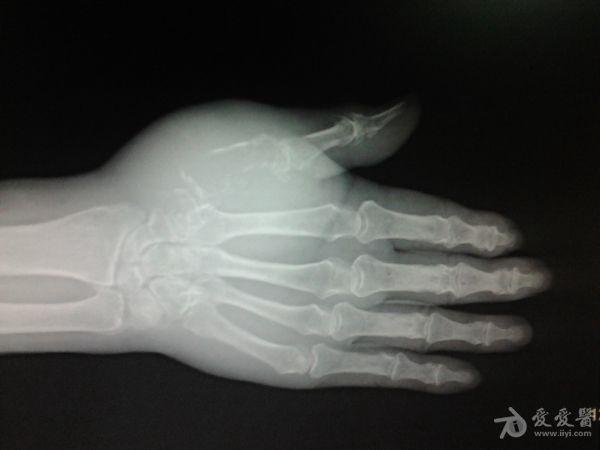

右第一掌骨、大多角骨肿瘤

男性患者,81岁,右手肿痛3个多月。无任何其它症状。体查:右手第一掌骨部肿胀明显,第一指活动受限,余四指活动可,腕关节活动小部分受限,活动时会痛。影像学检查如下。活检示:弥漫性大B细胞淋巴瘤。大家看看需不需要截肢?现在有人主张手术;有人主张不手术,直接化疗。大家有什么看法?